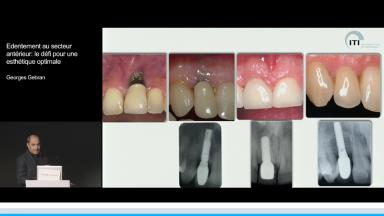

Edentement au secteur anterieur: le défi pour une esthetique optimale

A partir de la description des facteurs de risque esthétique du bloc incisivo-canin maxillaire, de la présence d’os et de gencive autour des implants, le conférencier présente une succession de cas cliniques décrivant ses procédures chirurgicales et prothétiques.

• de déterminer le bon timing de chirurgie implantaire post extractionnelle

• de réfléchir sur la préservation à moyen-long terme de l’os autour des implants